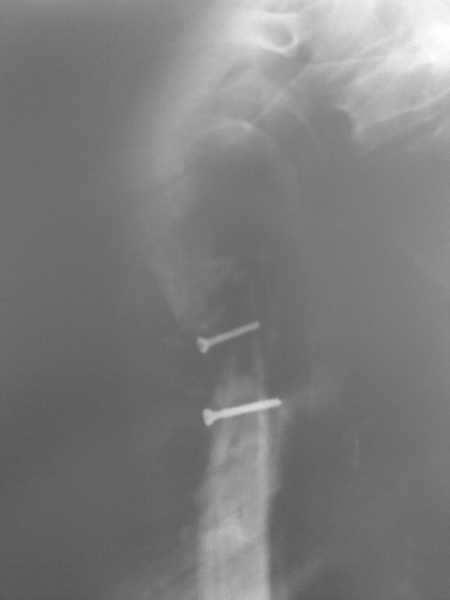

Здравствуйте, коллеги!!! К нам в отделение госпитализирован пациент 39 лет с клинико-рентгенологической картиной ложного сустава в/3 плечевой кости! Снимки прилагаются! Предистория такова: около года назад получил оскольчатый перелом в/3 плечевой кости. В одной из московских больниц выполнен остеосинтез пластиной, через несколько месяцев выполнен реостеосинтез, опять же пластной...., причины реостеосинтеза со слов пациента таковы - "доктору не понравилась как лежит пластина и он ее переложил..." - два месяца назад выполнено удаление фиксатора. Никаких выписок у больного нет. Около недели назад больной ударился областью плечевого сустава, появились боли, в связи с чем он обратился в травмопункт, откуда направлен к нам. Клинически у пациента имеется подвижность в области в\3 плеча, костная крепитация, умеренная болезненность в в/3 плеча при движениях, атрофия дельтовидной мышцы. На следующей недели планируем пациента опериравать. Коллеги, у нас возникло несколько вопросов, если не затруднит, то посоветуйте и подскажите... Мы планируем выполнить закрытый блокируемый остеосинтез, скажите пожалуйста, нужно ли в этом случае, на ваш взгляд, выполнять костную пластику или достаточно выполнить рассверливание костномозгового канала и заштифтовать толстым гвоздем, нужно ли пытаться удалить винты??? У нас в отделении идут дискуссии по этому поводу, придти к общему знаменателю не можем, поэтому и обращаемся к Вам!!! На основании ваших отзывов мы и примем окончательное решение!!! Спасибо!!! Очень ждем Ваших комментариев!!!

1. жизнеспособность головки плечевой кости, которая может быть установлена при КТ плечевого сустава. Если головка нежизнеспособная, то единственной альтернативой артродезу в данном случае является онкологический плечевой протез

2. характер ложного сустава и состояние костных отломков: четкая рентгенологическая картина гипотрофического (аваскулярного) ложного сустава с выраженным склерозом концов отломков и значительным дефектом костной ткани диктует необходимость введения в область ложного сустава остеоиндутивного материала (если бы не было значительного дефекта и склероза концов отломков в межотломковую область можно было бы ввести костную крошку, полученную при рассверливании костномозгового канала). В данном случае значительный дефект кости и плохое состояние концов требует: а)«освежения концов отломков», б) введения в область ложного сустава васкуляризированого костного трансплантатата, либо свободного костного аутоторансплантата, либо выполнение дистракционного остеосинтеза («костного транспорта»). При этом Вам естественно придется «открывать» область перелома, а значит Вы легко удалите винты.

3. состояние костной ткани поврежденного сегмента: в данном случае костная ткань остеопорозна, с многочисленными «дырами» от винтов, ранее фиксировавших пластины. Поэтому фиксировать пластиной третий раза нецелесообразно. Остаются 2 метода: блокированный штифт для проксимального плеча (Т2 страйкер или аналоги), либо аппарат внешней фиксации (чем лучше владеете).

Провести штифт в дистальный отломок закрыто вряд ли удастся: «сосулькообразный» конец отломка, запаянный костномозговой канал, дополнительное препятствие в виде 2 винтов.